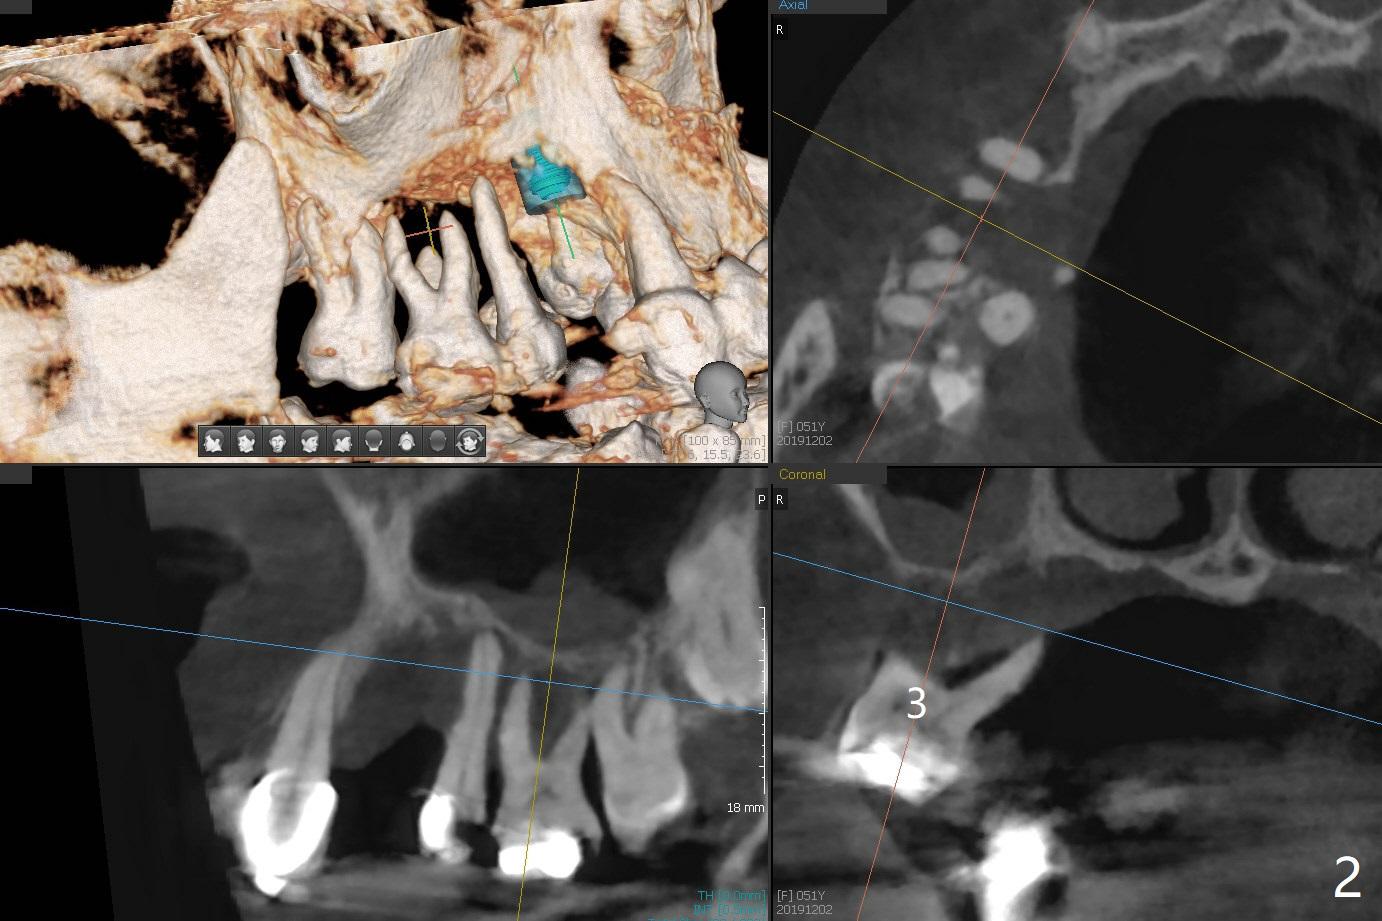

A 51-year-old woman has poor dentition with chronic periodontitis (Fig.1). She has financial constraint, but refuses RPD, insisting upon UR posterior implants first. After discussion of severe bone loss, she agrees with bone graft first (Fig.2-4). Since the bone atrophy is the most severe at #3 (Fig.5 coronal section; L: lingual), sinus lift (Fig.6 arrow) is conducted after extraction (black). Use sticky bone (Fig.7 red circles) and Titanium-reinforced Cytoplast (white) for socket preservation. Or if Magicore is able to achieve primary stability (Fig.8 green), an abutment (pink) will be placed for an immediate provisional (white). The latter are capable of holding bone graft in place. Since bone loss at #2 and 4 is less severe (Fig.9 sagittal section), their roots will act as walls to keep bone graft (Fig.11) in place after #3 extraction (Fig.10).